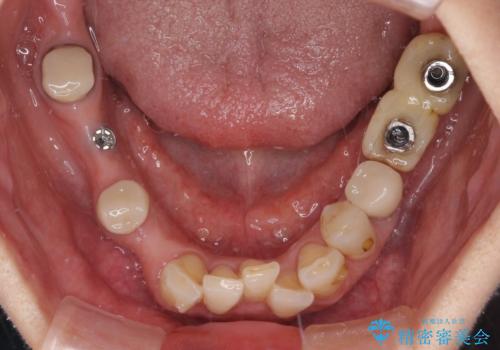

- 以前通院していた医院で、奥歯のインプラント埋入、前歯部のインビザライン矯正を行ったものの、そのまま放置してしまったとのことで来院された患者様です。

下顎前歯や上顎奥歯などをワイヤー装置により部分矯正を行い、歯列を整えた上でインプラン部分を含めてオールセラミッククラウンにて補綴治療を行うこととしました。

インプラント上の仮歯がボロボロになり、前歯に非常に負担のかかる状態であったため、早急に奥歯の仮歯を修復し、矯正治療、奥歯の補綴治療、前歯の補綴治療と順々に進めて行きました。